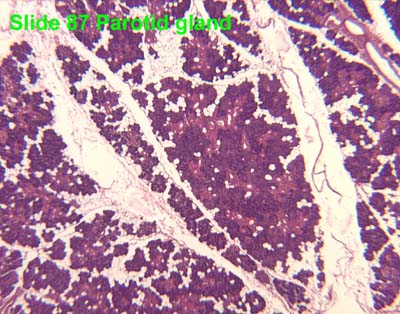

Slide 87 Parotid.

The parotid gland is a pure serous gland and thus made up of all serous acini . Note the prominent granules of the acinar cells.